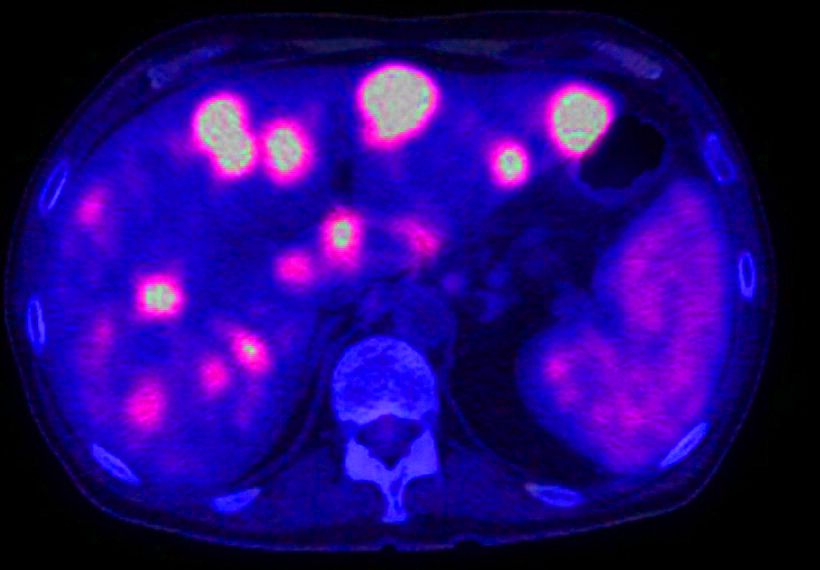

Σε έναν ασθενή στον οποίο έχει αντιμετωπισθεί ο πρωτοπαθείς όγκος, ο μοναδικός τρόπος για να διαγνωστούν τυχών μεταστάσεις νωρίς και πριν δώσουν συμπτώματα είναι να ακολουθεί τον κατάλληλο τακτικό έλεγχο που έχει ορίσει ο ογκολόγος ιατρός του. Αυτό συνήθως περιλαμβάνει εξετάσεις αίματος και απεικονιστικές εξετάσεις όπως αξονική, υπέρηχο, μαγνητική τομογραφία ή PET. Οι μεταστάσεις στο ήπαρ μπορεί να εμφανιστούν οποιαδήποτε στιγμή μετά από μήνες ή πολλά χρόνια, κατά τη διάρκεια ή ακόμα και μετά το τέλος μιας χημειοθεραπευτικής αγωγής.

Ιδανική περίπτωση θεωρείτε η επέμβαση σε ασθενείς με μεταστάσεις μόνο στο ήπαρ που έχουν μόνο μία εστία μικρότερη από 5εκ ή μέχρι τρείς εστίες μικρότερες από 3εκ. Σήμερα όμως υπάρχουν μελέτες που δείχνουν ότι μπορούμε να επέμβουμε ακόμα και όταν υπάρχουν ταυτόχρονα μεταστάσεις και εκτός ήπατος όπως για παράδειγμα σε λεμφαδένες, στο περιτόναιο, στο επινεφρίδιο κ.α. με ενθαρρυντικά αποτελέσματα αν γίνει πλήρης αφαίρεση όλων των βλαβών.